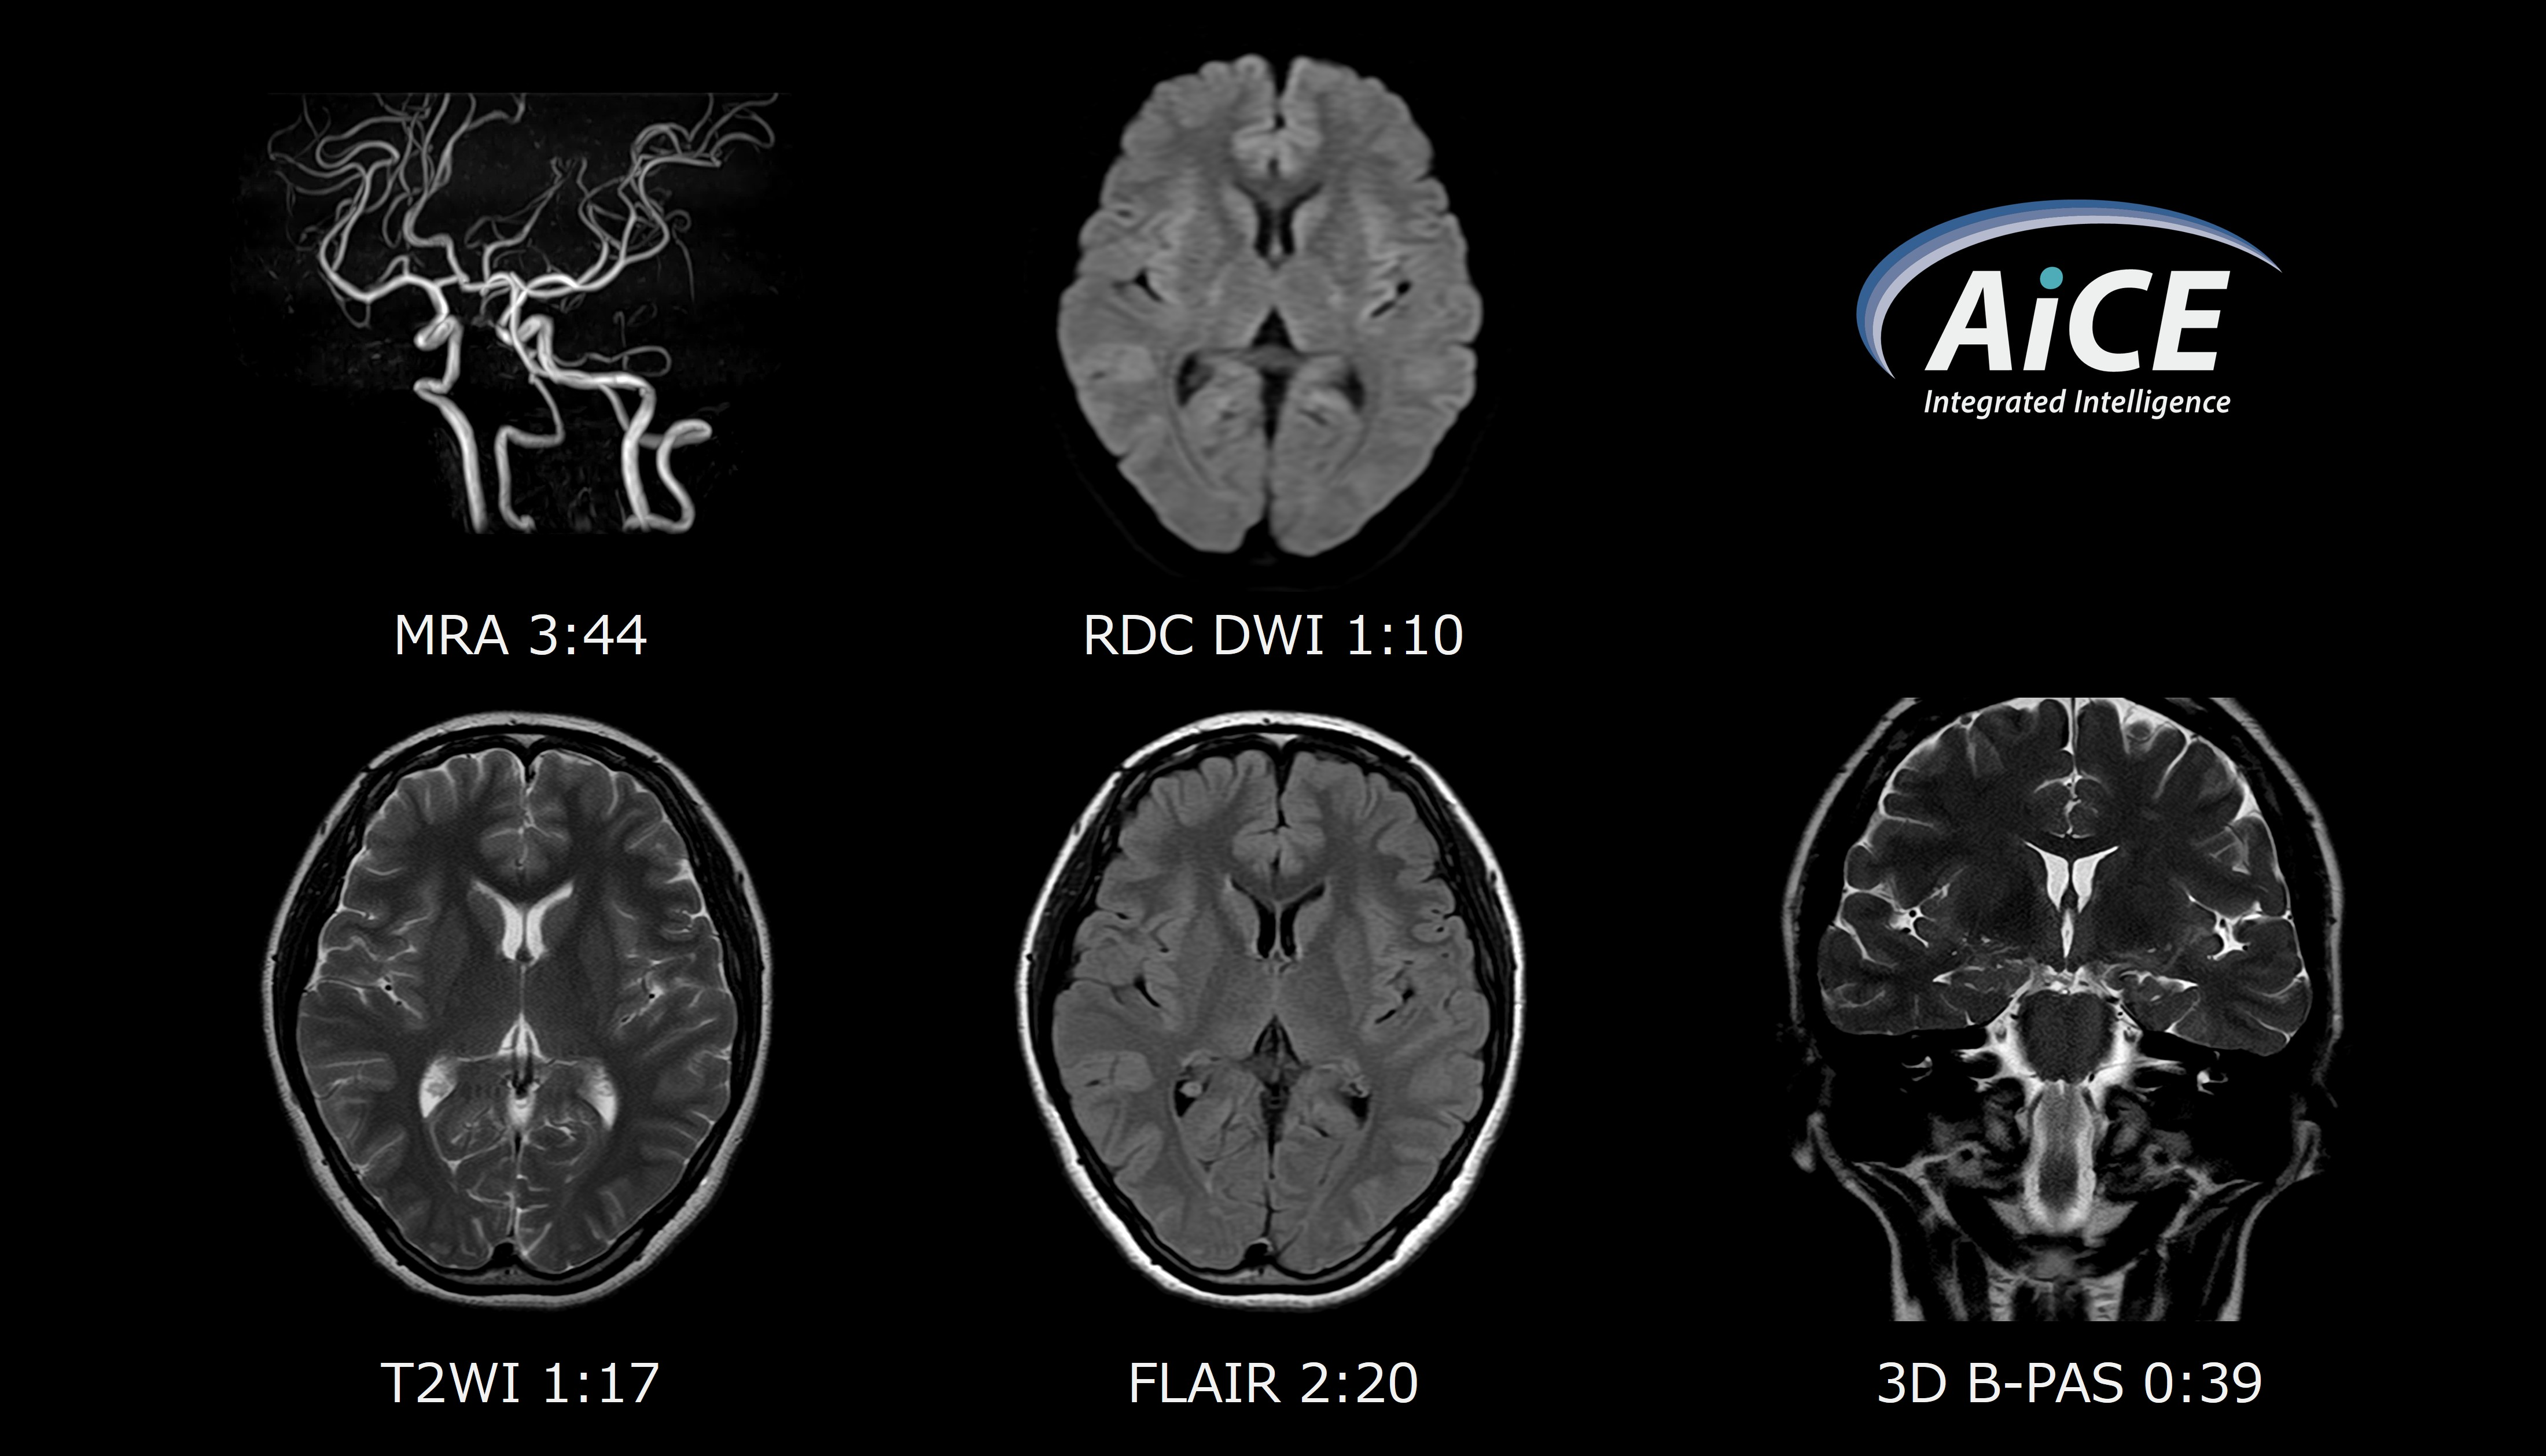

撮像時間短縮の大きな要因は、パラレルイメージング法「SPEEDER」、圧縮センシング法「Compressed SPEEDER(CS)」にAiCEを併用できる点です。さらに、頭部MRA撮像では、3D撮像高速化技術「Fast 3Dモード」とAiCEを組み合わせることで、画質を損なうことなく36%程高速化しました。(Fig.1)当院では頸部MRAを追加するケースも多く、こうした場面で恩恵を強く感じています。

画質向上では、特にFLAIRが劇的に変化しました。原理上SNRが得づらい撮像ですが、AiCEによるSNR向上によってパラメータの調整幅も広がり、さらに新しいIRパルス印加パターンである「Clusterモード」の追加により、各組織のコントラストも向上しています。(Fig.2)

高画質化の面では、新たに搭載されたDWIの歪み改善技術である「RDC DWI」による改善効果が顕著であり、ルーチン検査において全例で使用しています。類似機能に「FASE DWI」もありましたが、コントラスト変化や撮像時間延長が伴うため、ルーチンでの使用が困難でした。一方、「RDC DWI」は、コントラストに影響を与えることなく、撮像時間の延長も約10秒にとどまり、実用性が非常に高いと感じています。DWIは非常に重要なシーケンスであり、わずかな時間延長で画質を大きく改善できる点は、臨床上、大きなインパクトになりました。(Fig.5)